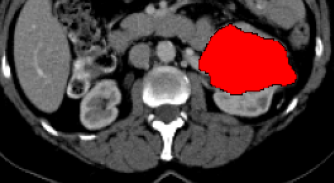

Current research on deep learning for medical image segmentation exposes their limitations in learning either global semantic information or local contextual information. To tackle these issues, a novel network named SegTransVAE is proposed in this paper. SegTransVAE is built upon encoder-decoder architecture, exploiting transformer with the variational autoencoder (VAE) branch to the network to reconstruct the input images jointly with segmentation. To the best of our knowledge, this is the first method combining the success of CNN, transformer, and VAE. Evaluation on various recently introduced datasets shows that SegTransVAE outperforms previous methods in Dice Score and $95\%$-Haudorff Distance while having comparable inference time to a simple CNN-based architecture network. The source code is available at: https://github.com/itruonghai/SegTransVAE.